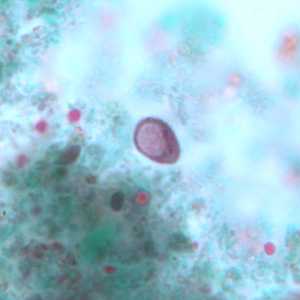

E. nana cyst stained with trichrome.

Figure A: Cysts of E. nana stained with trichrome.

Figure B: Cyst of E. nana stained with trichrome.

Figure C: Cyst of E. nana stained with trichrome.

Figure D: Cyst of E. nana stained with trichrome.